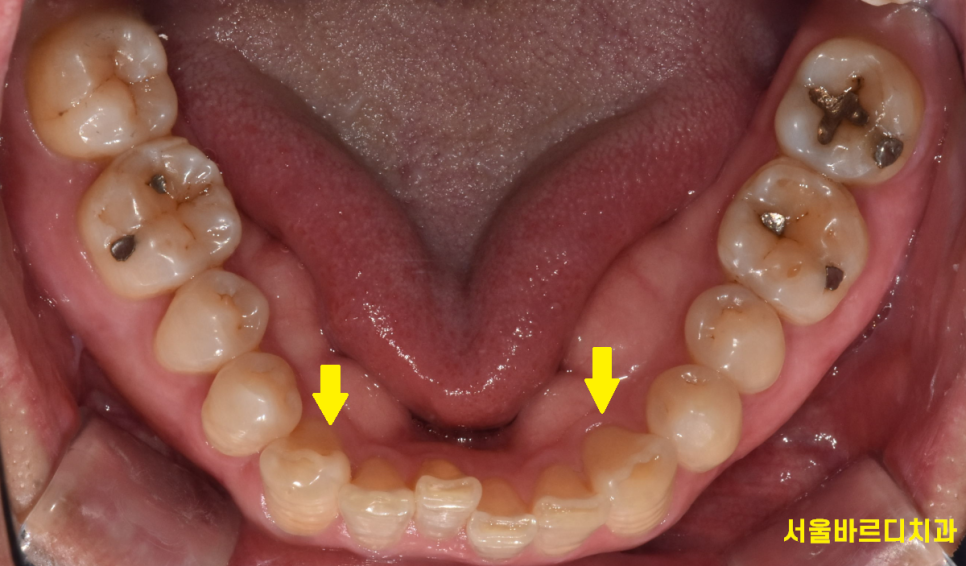

치아 상태, 골격 구조, 나이 , 생활 습관 등 말이죠!

230613 본원 50대 교정 환자분입니다! 잇몸이나 고려할 요소가많긴 하지만 충분히 진행 하실 수 있어요~

그렇다면 청소년들의 치아 교정 속도가 빨라야하는데

꼭 그렇지도 않습니다.